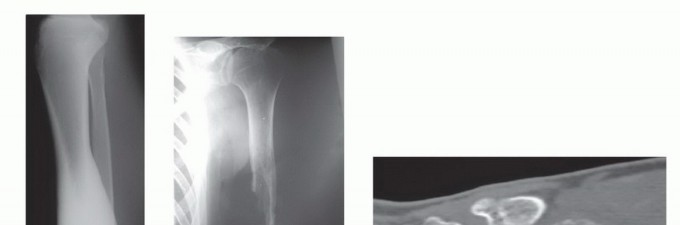

- الأشعة السينية العادية (Plain Radiography): تُظهر صور الأشعة السينية العادية (FIG 4AB) العيب العظمي وحجمه، وتساعد في تقييم بنية العظم المحيطة.

- التصوير المقطعي المحوسب (CTA): يُستخدم التصوير المقطعي المحوسب (FIG 4C) عندما تكون الأوعية الدموية غير واضحة، حيث يوفر صورًا مفصلة للأوعية الدموية في المنطقة المستقبلة.

تصوير عيوب العظام

- أ. صورة شعاعية عادية للظنبوب تُظهر ساركوما عظمية كبيرة منخفضة الدرجة في الجزء الجذعي.

- ب. صورة شعاعية عادية للذراع تُظهر فقدانًا كبيرًا للعظم وكسرًا مرضيًا مرتبطًا بالتهاب العظم والنقي الحاد في جسم العضد.

- ج. إعادة بناء مقطعي محوسب إكليلي للساعد البعيد يُظهر ساركوما عظمية في الكعبرة البعيدة.